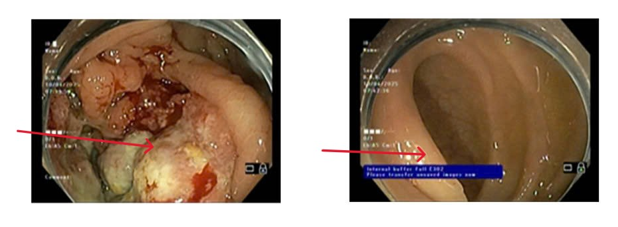

- Nội soi dạ dày: Niêm mạc hang vị phù nề xung huyết, rải rác có vài trợt nông và có hình ảnh viêm teo niêm mạc dạ dày (C2), bờ teo lan qua góc bờ cong nhỏ. Mặt trước hang vị có ổ loét kích thước ~ 0.8cm, bờ phù nề, đáy phủ giả mạc trắng

Hình 1: Hình ảnh nội soi dạ dày có tổn thương phù nề xung huyết tại niêm mạc hang vị (bên trái) và ổ loét ở mặt trước hang vị (bên phải)

- Nội soi đại tràng: Đoạn cuối hồi tràng niêm mạc mềm mại, không có loét. Manh tràng có sùi loét lớn, bờ thâm nhiễm cứng (sinh thiết). Đại tràng: Đại tràng chuẩn bị chưa sạch, còn dịch phân hạn chế quan sát. Phần quan sát được: Niêm mạc hồng, nhẵn, không có u, không có loét. Trực tràng: Niêm mạc hồng, nhẵn, không có u, không có loét.

Hình 2: Hình ảnh nội soi đại tràng có tổn thương sùi loét lớn bờ thâm nhiễm cứng tại manh tràng (bên trái) và hình ảnh niêm mạc mềm mại tại hồi tràng (bên phải)